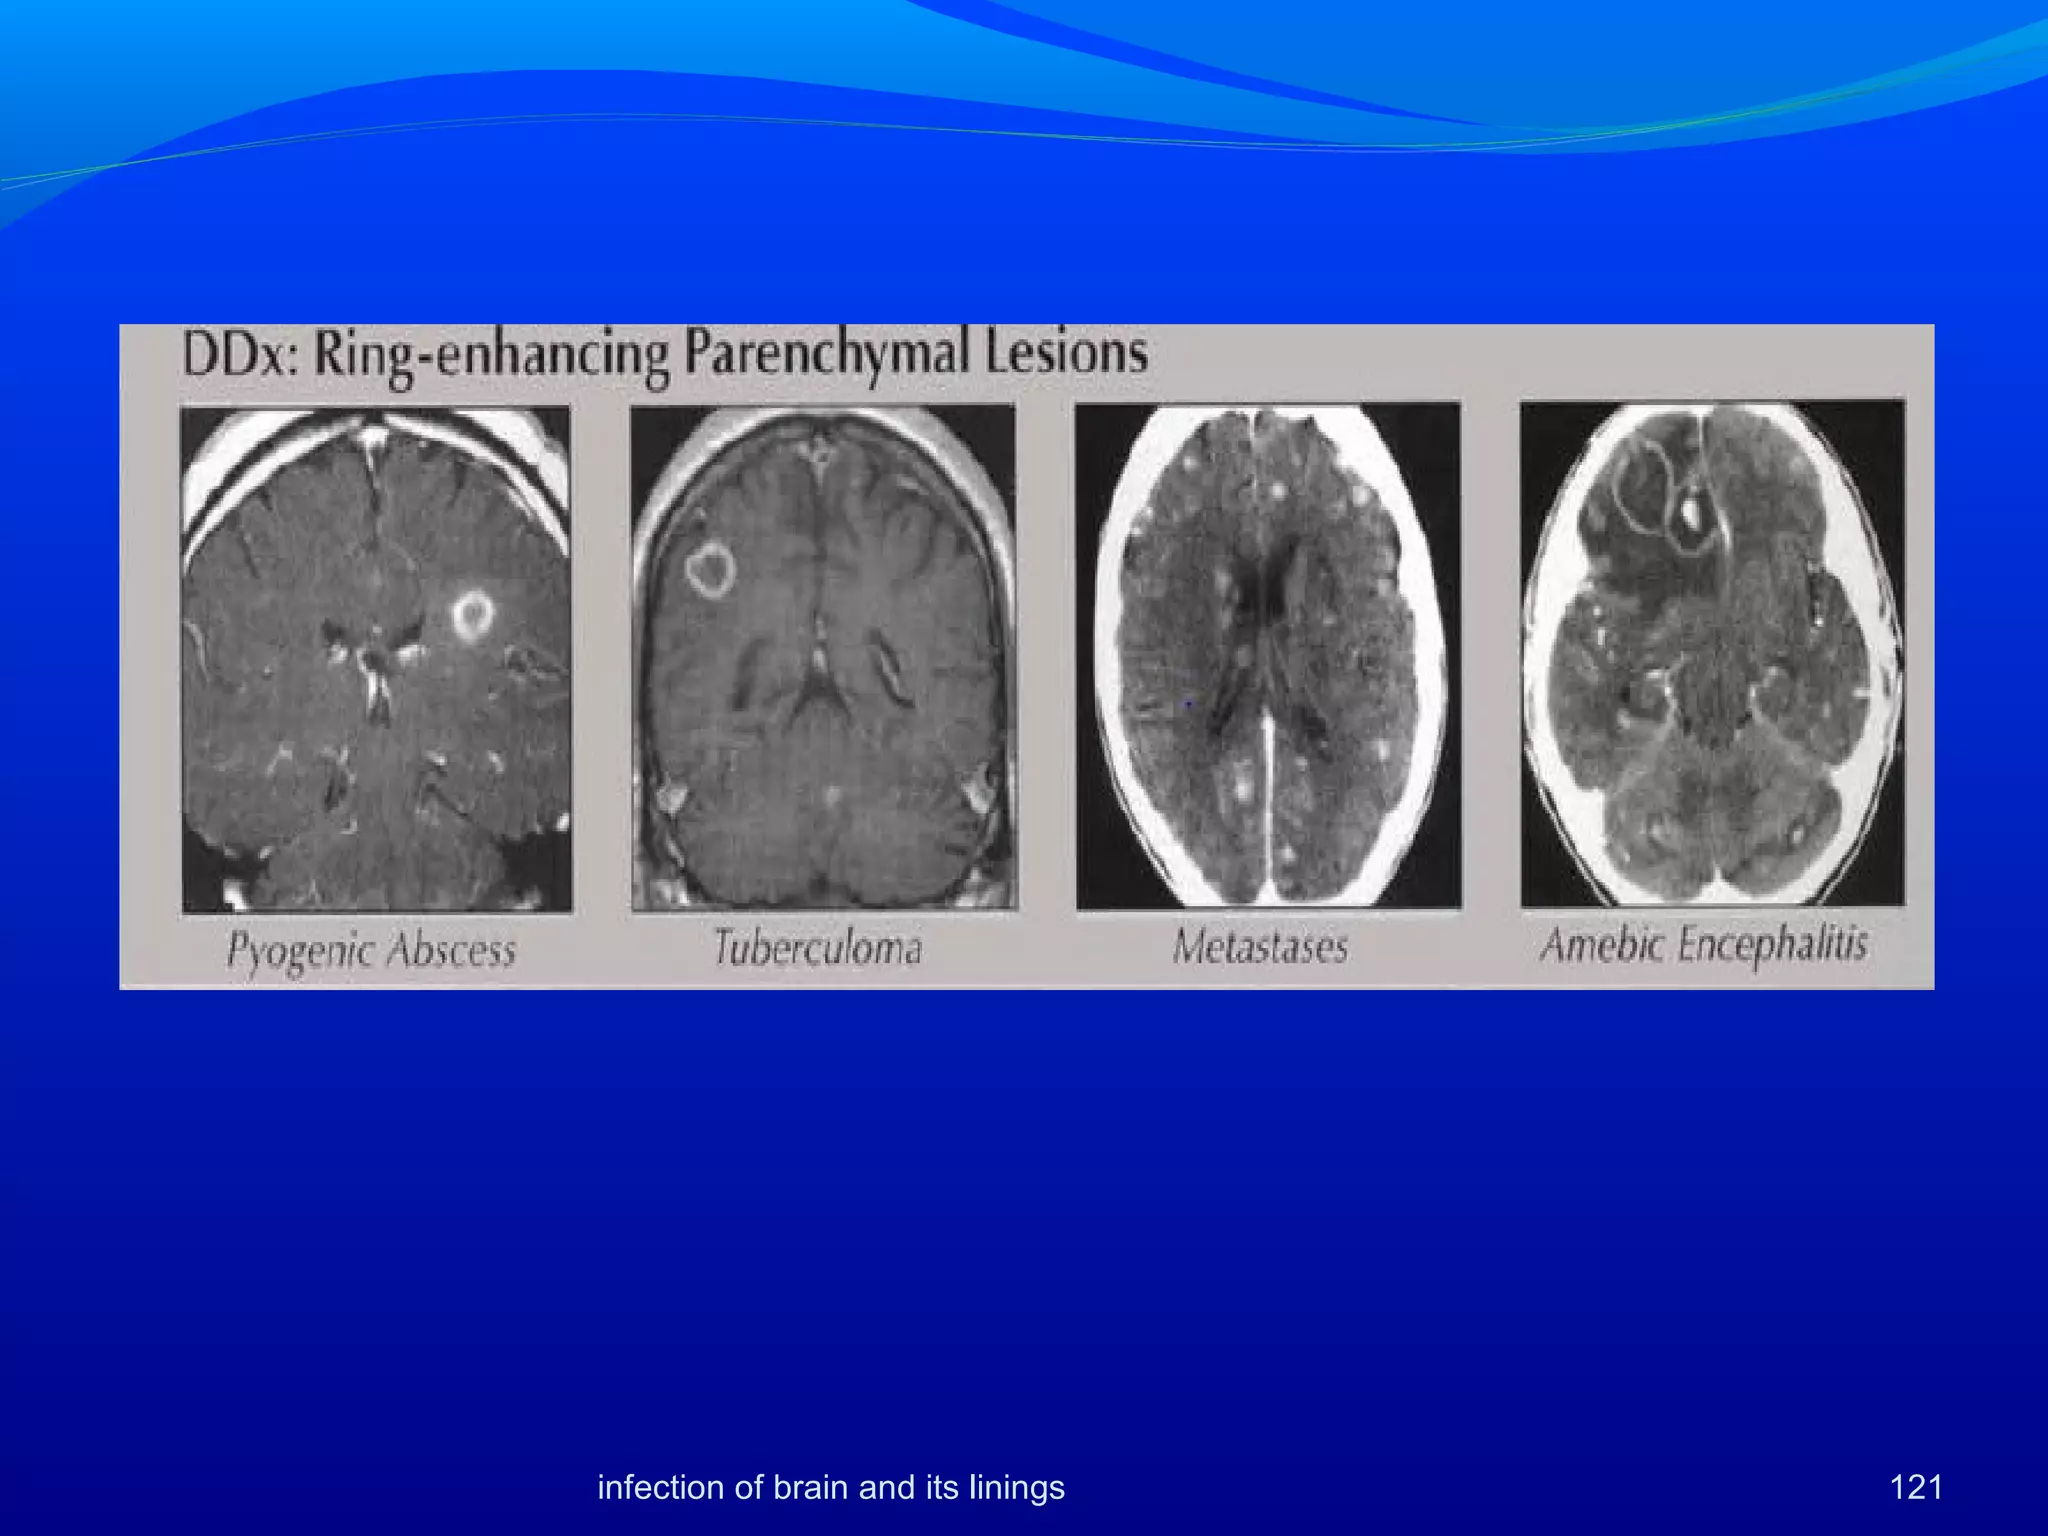

The most distinctive feature of abscess on imaging is the presence of

a smooth, thin capsule with a moderate amount of cerebral edema.

[57]

 It is located at the corticomedullary junction and usually extends

into the white matter.

Nonenhanced CT scans show a low-density area with mass effect and

compression of the ventricular system.

 rupture of the abscess into an adjacent ventricle {medially into the

ventricular system because the medial wall is thinner than the lateral

wall

Differential diagnosis

 necrotic primary brain tumor, cystic metastatic tumor, infarction,

resolving hematoma, cysticercosis, and thrombosed aneurysm

Thick, nodular enhancing

wall typical

History of trauma or vascular

lesion

• Blood products present

Enhancement often

incomplete ring

• Thick, nodular

enhancing wall typical

95infection of brain and its linings

Infarcts often show gyral enhancement, occasionally mimicking

ring enhancementThe MRI differential diagnosis of

abscess is similar to the CT diagnosis except for hematomas,

which can be recognized by their characteristic MRI signal

intensity patterns, depending on the age of the hematomas